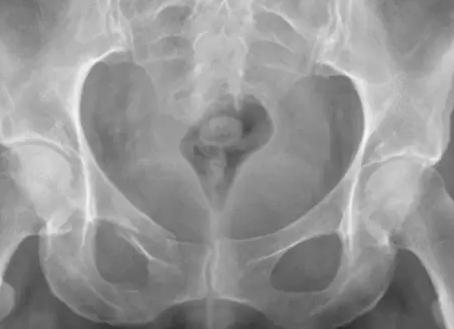

Опытный врач диагноз может поставить на основании жалоб и симптомов. Основной метод диагностики — рентгенография позвоночника; снимки делают во всех 3 проекциях. Перед рентгеном обязательно проводится очищение кишечника клизмой. На снимках остеофиты различаются четко. Здесь есть несколько стадий развития процесса: